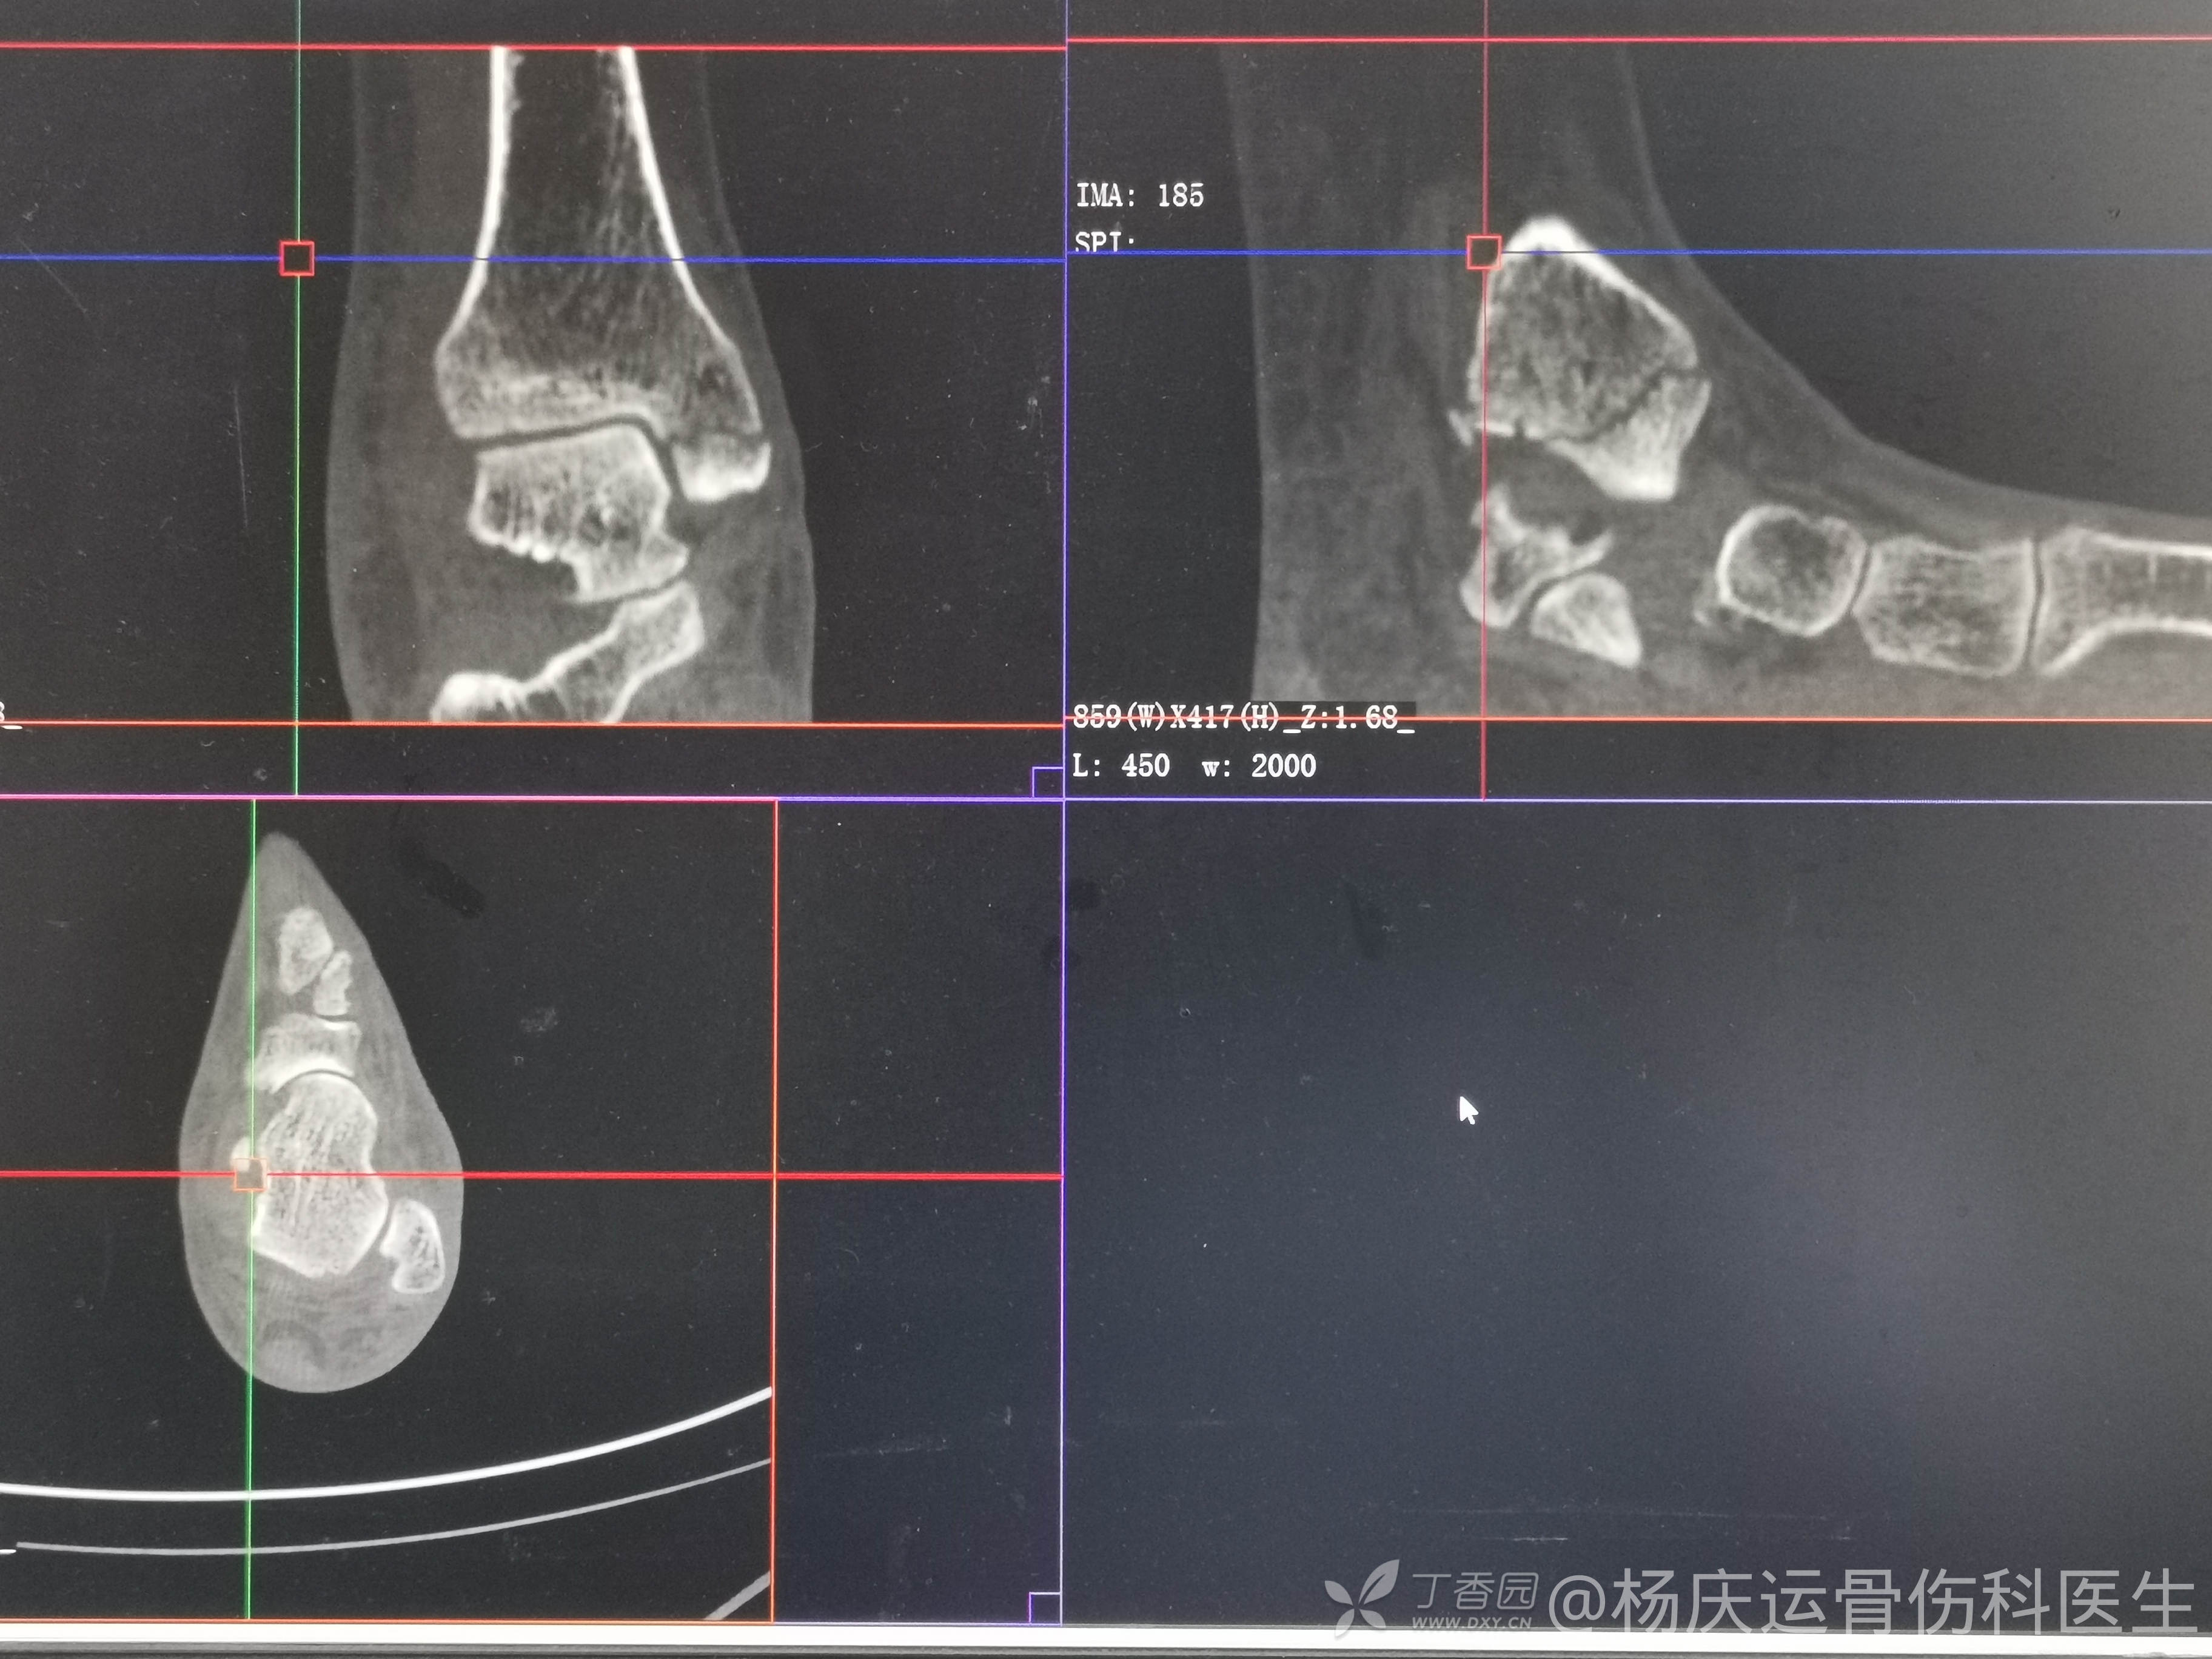

复位前CT